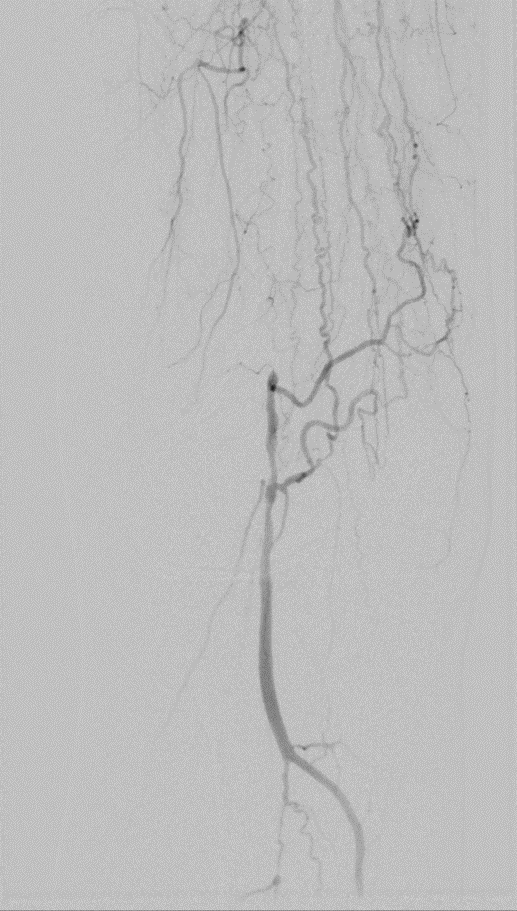

开通:以内膜下技术为主,逆穿是常用且有效的辅助手段。

预扩:充分预扩张至关重要,需逐级使用高压球囊,最终达到 6mm 直径,以获得足够的管腔。

支架植入:遵循“由远及近”原则,先放置远端 DES,再覆盖中段 VB,最后处理近端。利用 Eluvia 的可调节性优化重叠。

后扩:常规使用 6mm 高压球囊进行后扩张,确保支架充分贴壁和管腔获得。

用药:术中术后必须充分抗凝,推荐“双通道”抗栓方案(如利伐沙班+阿司匹林),以模拟 bypass 的血流动力学效果。